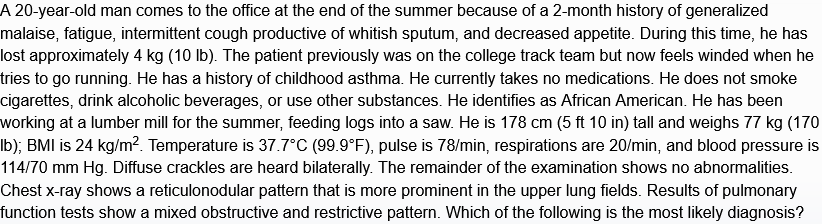

hypersensitivity pneumonitis

hypersensitvity pneumonitis - cause, features, dx, tx

inhalation of env/occupational antigens, usually animal (birds), fungi, bacteria, or inorganic chemicals leading to interstitual lung disease

acute - constitutional, flu-like sx, leukocytosisl; or more chronic - cough, dyspnea, fatigue, weight loss

diagnosed via hx & ct of chest showing fibrosis. also lymphocytosis on bronchoaleolar lavage, noncaseating granulomas on histopathology

avoid antigen, usually resolves spontaneously. can give glucocorticoids if symptoms persist. if refractory, may eventually require lung transplant